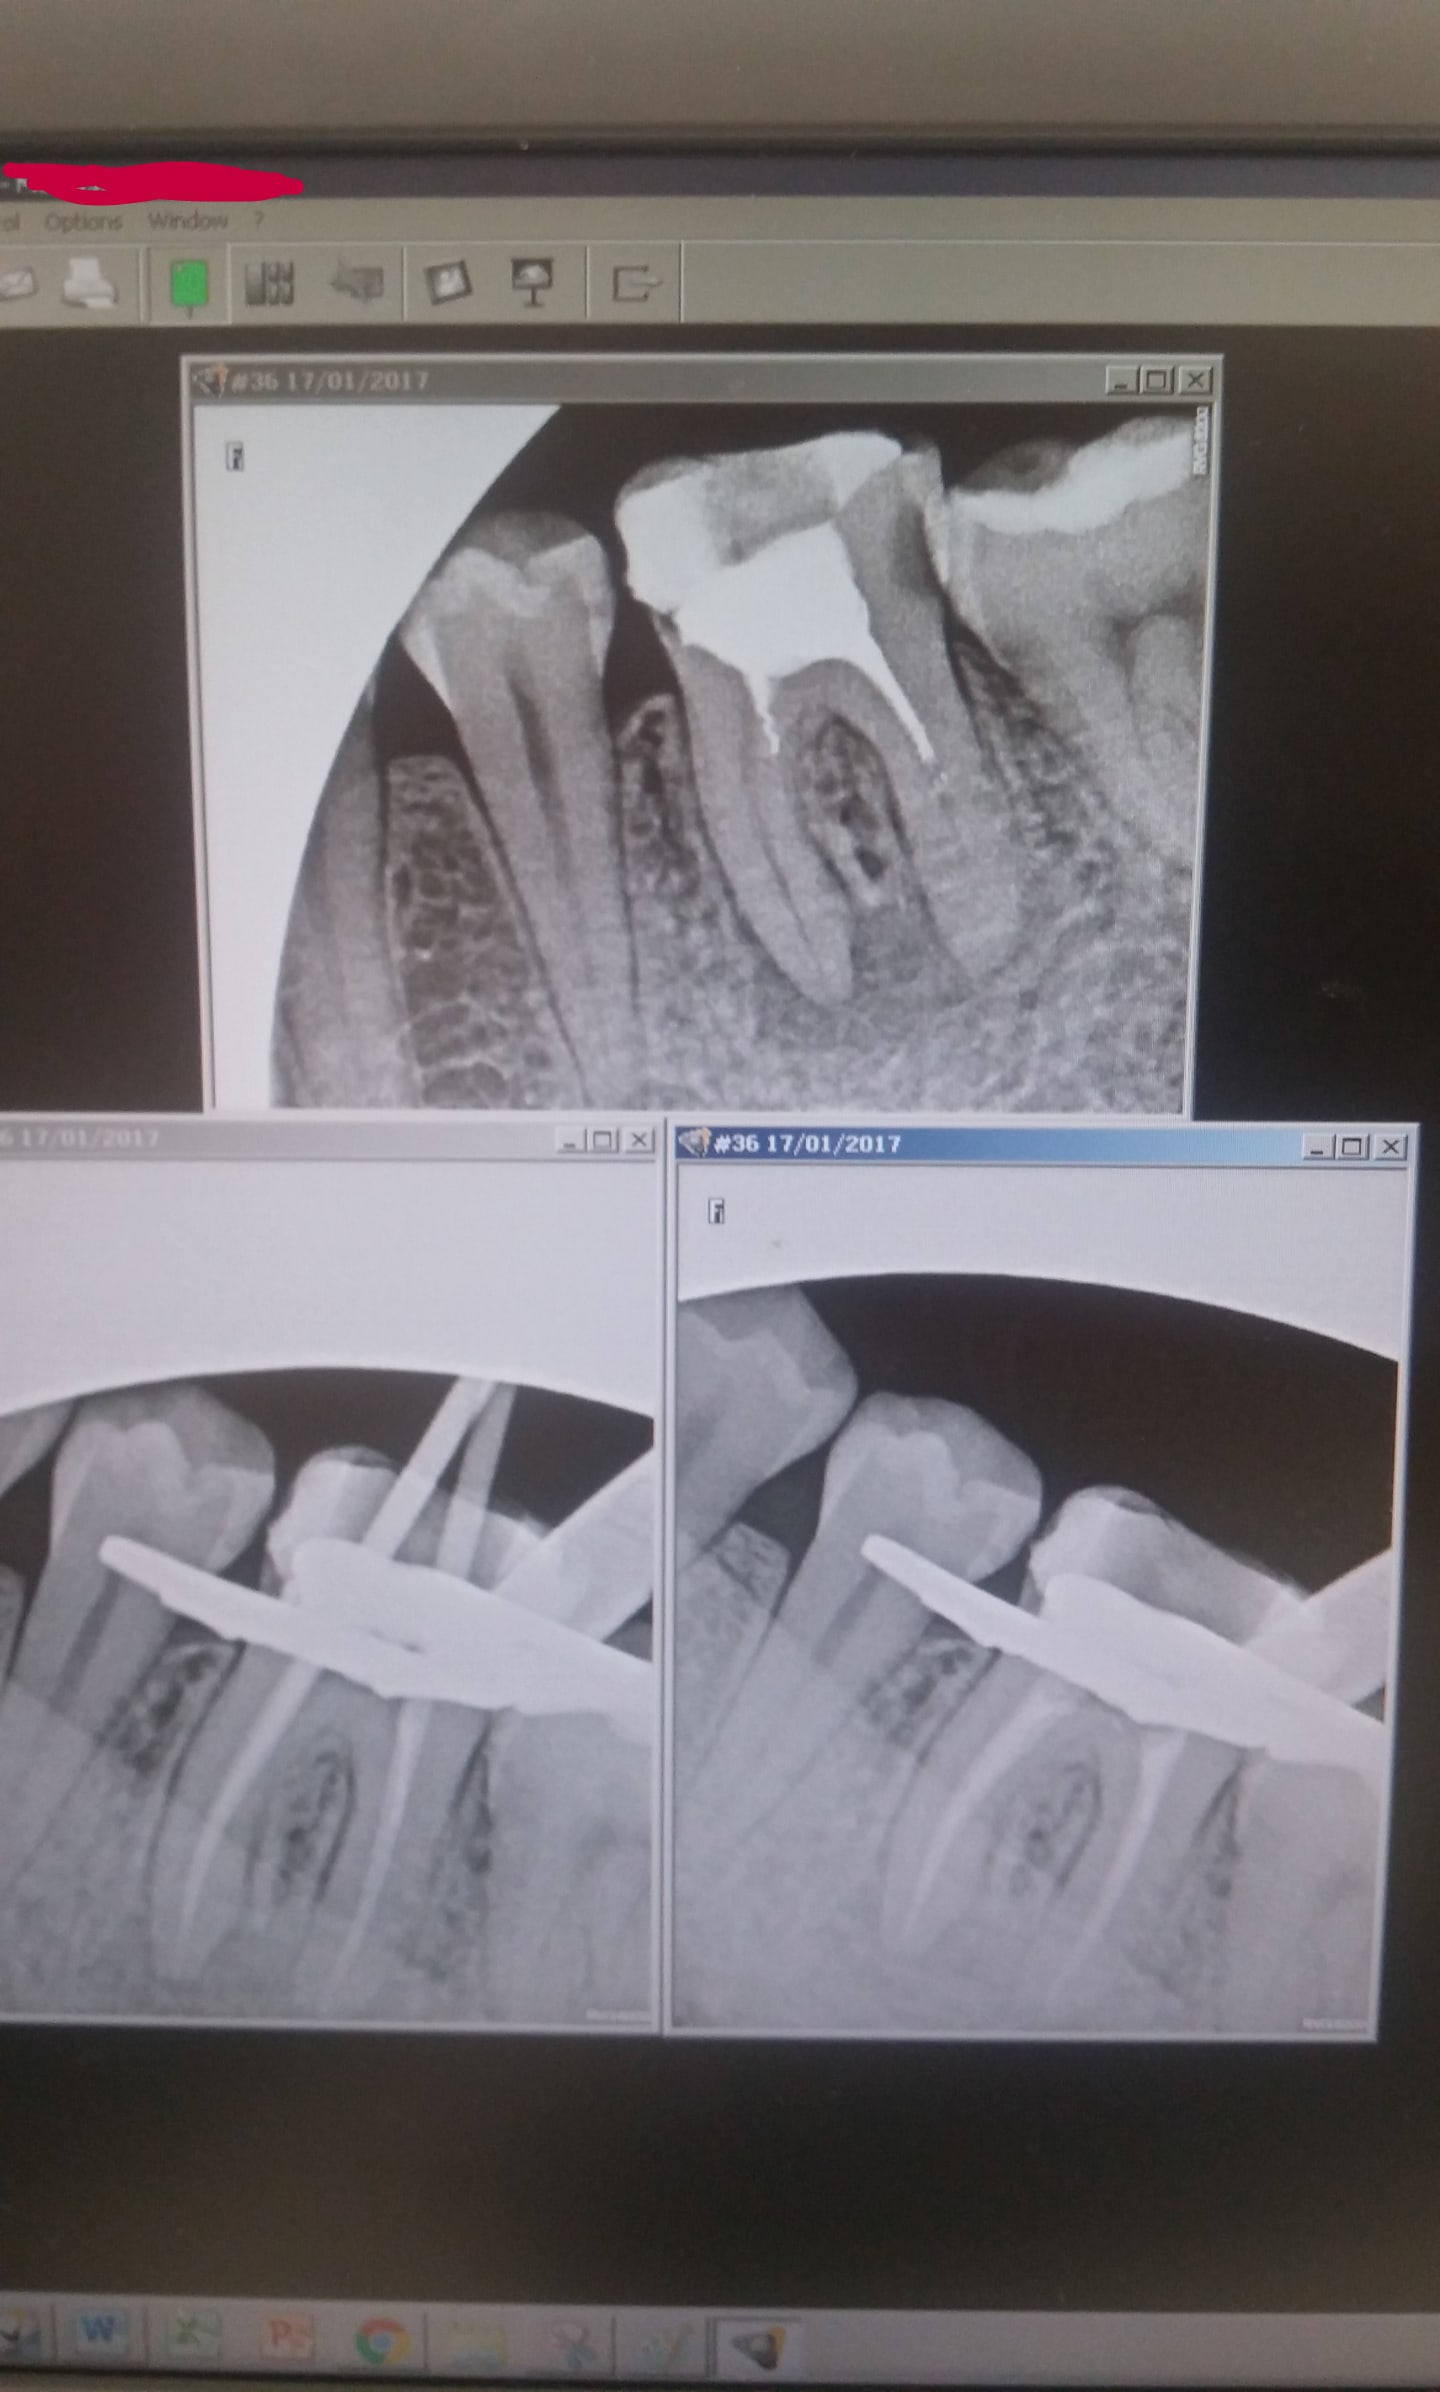

Lors de mes traitements et retraitements j'ai du mal à avoir une image radio aussi belle que celle de chicot et celle qu'on peut voir parfois sur le forum, dans les publications, sur le net etc..

Mes Endos ont l'air "fades", dans le sens où mes obturations ont l'air moins denses donc moins etanchrs, peut importe la technique et je me demande d'où vient le problème.

Par exemple aujourd'hui rte sur 36,obturation mixte sisteme b + thermocompaction, mais si je fais thermocompaction seul c'est kif kif.

Pour l'endo au départ du post elle est très bien c'est à mon avis une histoire de contraste.

Je vois que tu as le meme logiciel d'imagerie que le mien sers toi de la balance de contraste du panneau de controle !